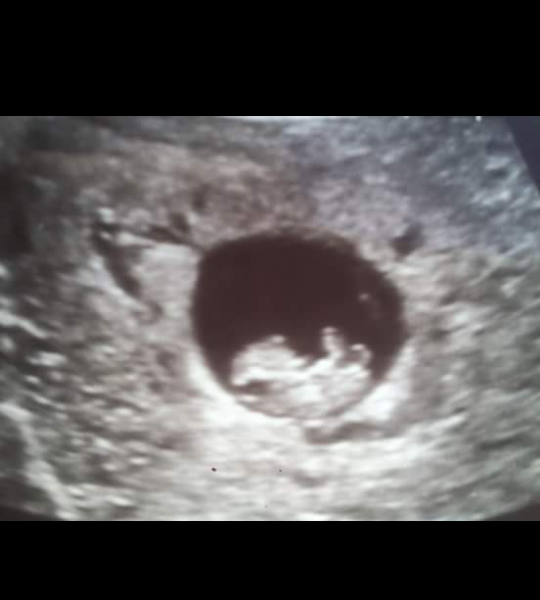

okay so I have a question. this was my ultrasound at about 9 weeks. I'm now 18 and 2 days and we find out the gender Monday and I cannot wait. well I really can't get twins out of my mind. I know that sometimes one is hidden in the beginning. do you think that's possible? I just can't stop thinking about twins and idk why

okay, I don't know why I can't stop thinking about it. probably because twins run in my family and my boyfriends family and Ive always wanted them Lol. At my first u/s they did say my uterus measured a little larger, if that means anything lol